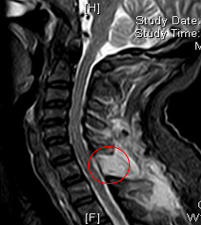

术前核磁检查颈胸段椎管内存在占位性病变,且脊髓已被挤压成线形。

若不尽快手术切除肿瘤,随着肿瘤持续增大,脊髓受压程度会不断加重,进而造成不可逆的神经损伤,最终甚至可能导致四肢瘫痪。接下来,脊柱外科一区主任、主任医师许宇霞带领团队成功为张淮实施了高难度颈胸段椎管内肿瘤切除术。术中快速病检提示肿块为“神经鞘瘤”,这类肿瘤多为良性肿瘤,手术切除后预后良好,复发率低。术后张淮恢复良好,原有颈肩疼痛消失,左上肢麻木无力及右下肢行走无力等症状均显著改善。

术后复查核磁检查,颈胸段椎管内肿瘤已切除干净。